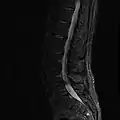

MRI